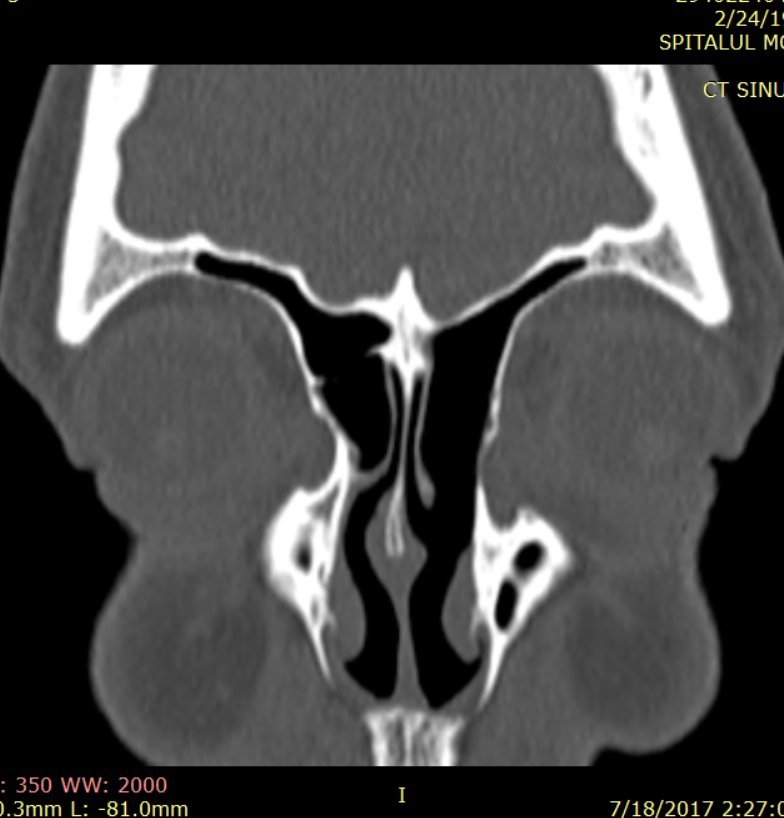

Examenul clinic şi endoscopic ORL, precum şi examenele imagistice complementare (CT/RMN) stabilesc diagnosticul de formaţiune tumorală etmoid antero-posterior stâng extinsă la sinusurile maxilar şi frontal stâng, cu încărcare intensă postcontrast, diametrul cranio-caudal de 35mm.

Pacienta efectuase încă din anul 2015 un examen RMN craniocerebral pentru explorarea lojei hipofizare în contextul SIADH, în care se putea vizualiza cu uşurinţă patologia tumorală rinosinusală, însă examenul ORL efectuat la acea dată a stabilit diagnosticul de polipoză nazală unilateral – fig. 1

Fig. 1: examen RMN craniocerebral cu substanță de contrast efectuat în anul 2015